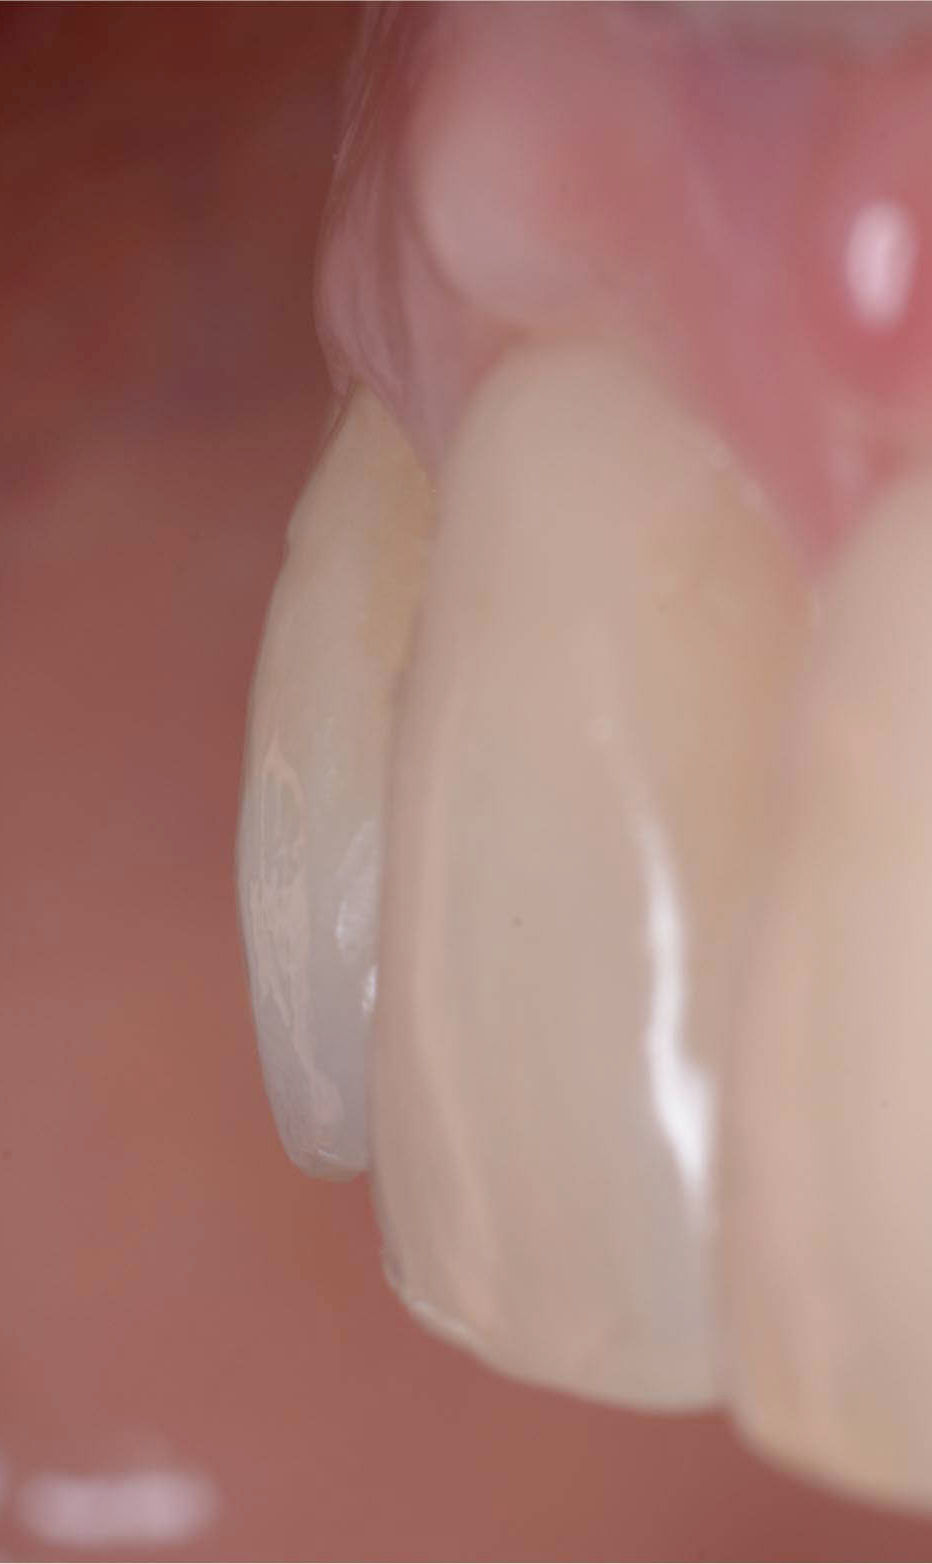

Initial case: frontal view.